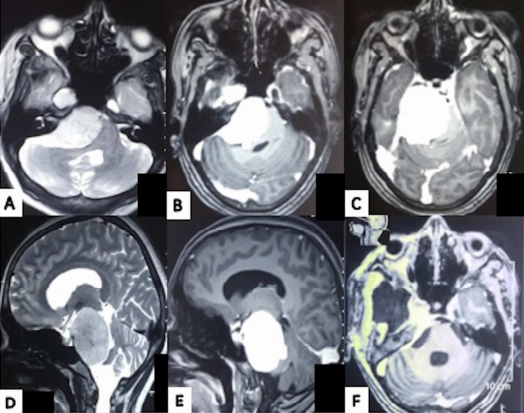

面神经麻痹和三叉神经感觉减退均有轻微好转。图示:(A)32岁女性,左侧颈面部运动障碍,轴向T2加权SEMR图像显示左侧岩斜坡脑膜瘤压迫脑干。图示:(A)32岁女性,左侧颈面部运动障碍,...

岩斜脑膜瘤(PCMs)由于其与脑干、主要血管结构、穿支和颅神经的关系,一直是颅底外科医生面临的挑战。手术入路的选择取决于肿瘤的位置、范围、大小、患者年龄、术前听力和面神...